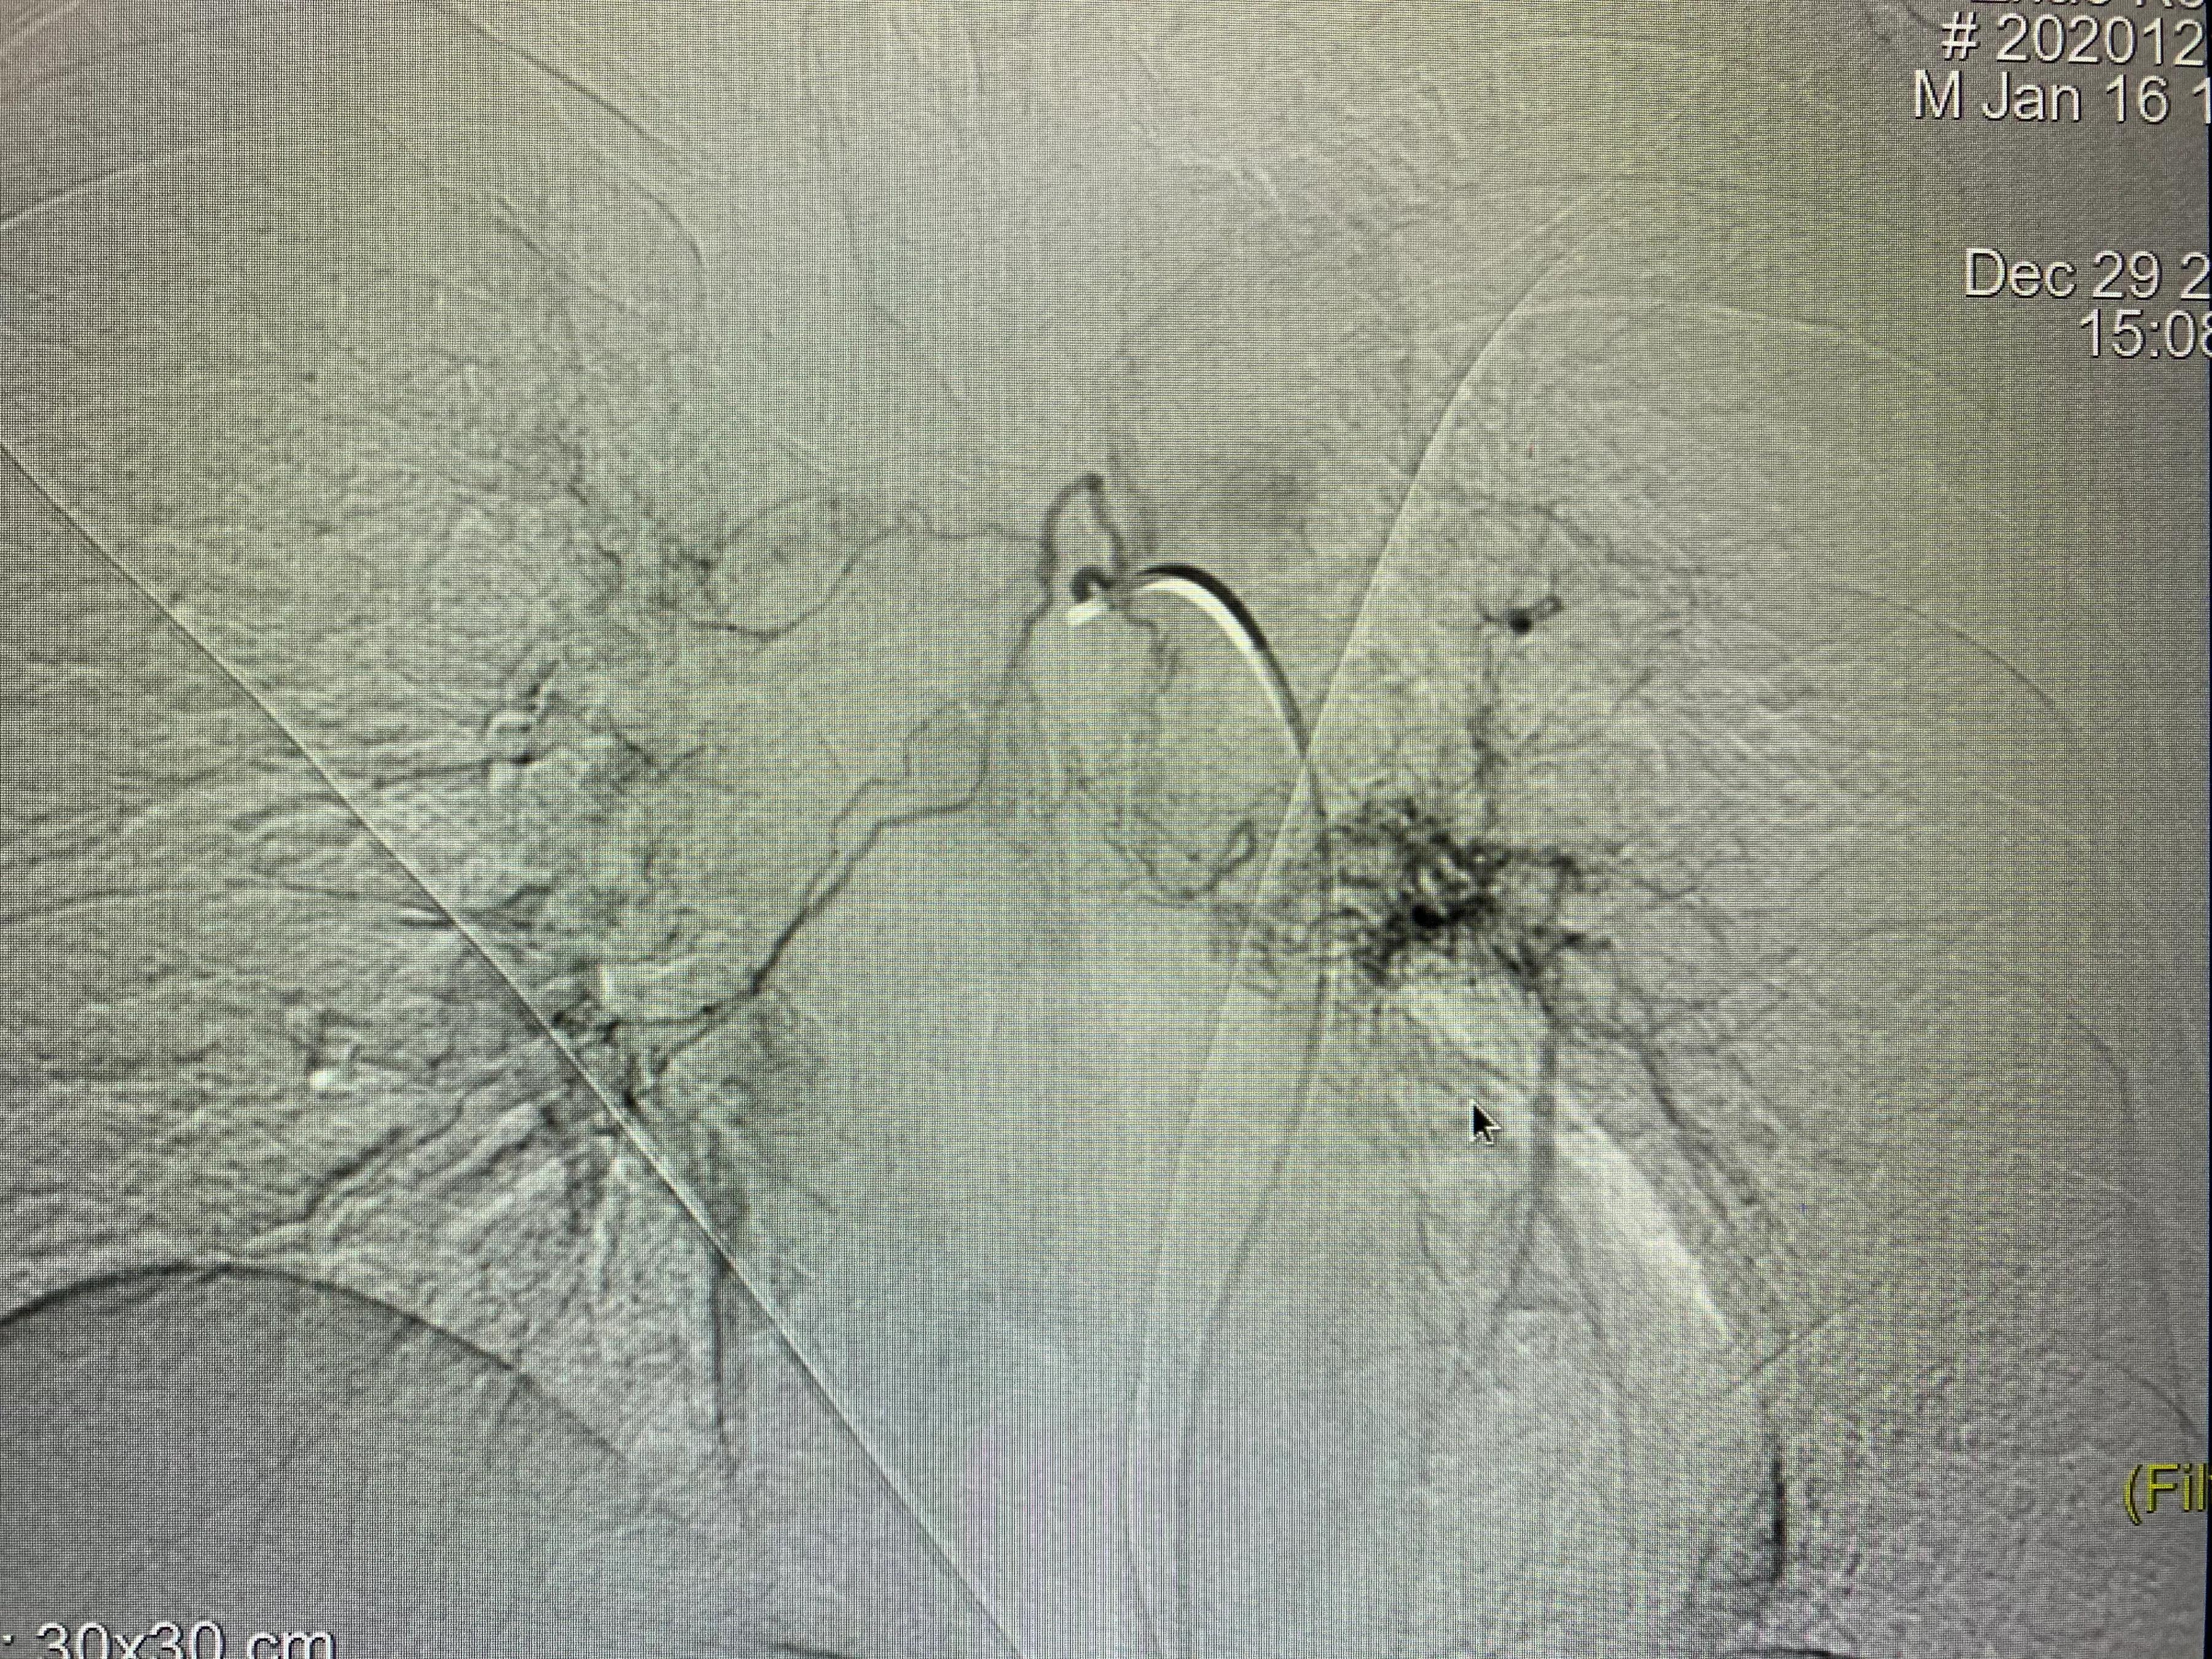

老年男性患者,左肺腺癌,化疗期间出现了咯血,术中可见左侧支气管动脉、左侧多支肋间动脉及左侧胸阔内动脉均参与肿瘤的血供,并可见以上动脉-肺动脉瘘,经肿瘤供血动脉灌注化疗药并且进行栓塞,术后未再出现咯血,一个月复查ct提示肿瘤较前明显减小,阻塞症状较前缓解。微创介入即经导管灌注化疗栓塞治疗肺肿瘤能够有效治疗肿瘤并且缓解肿瘤引起的一系列并发症,如咯血、阻塞性肺炎等,当然,肿瘤的治疗是综合治疗,需要多学科的共同参与。